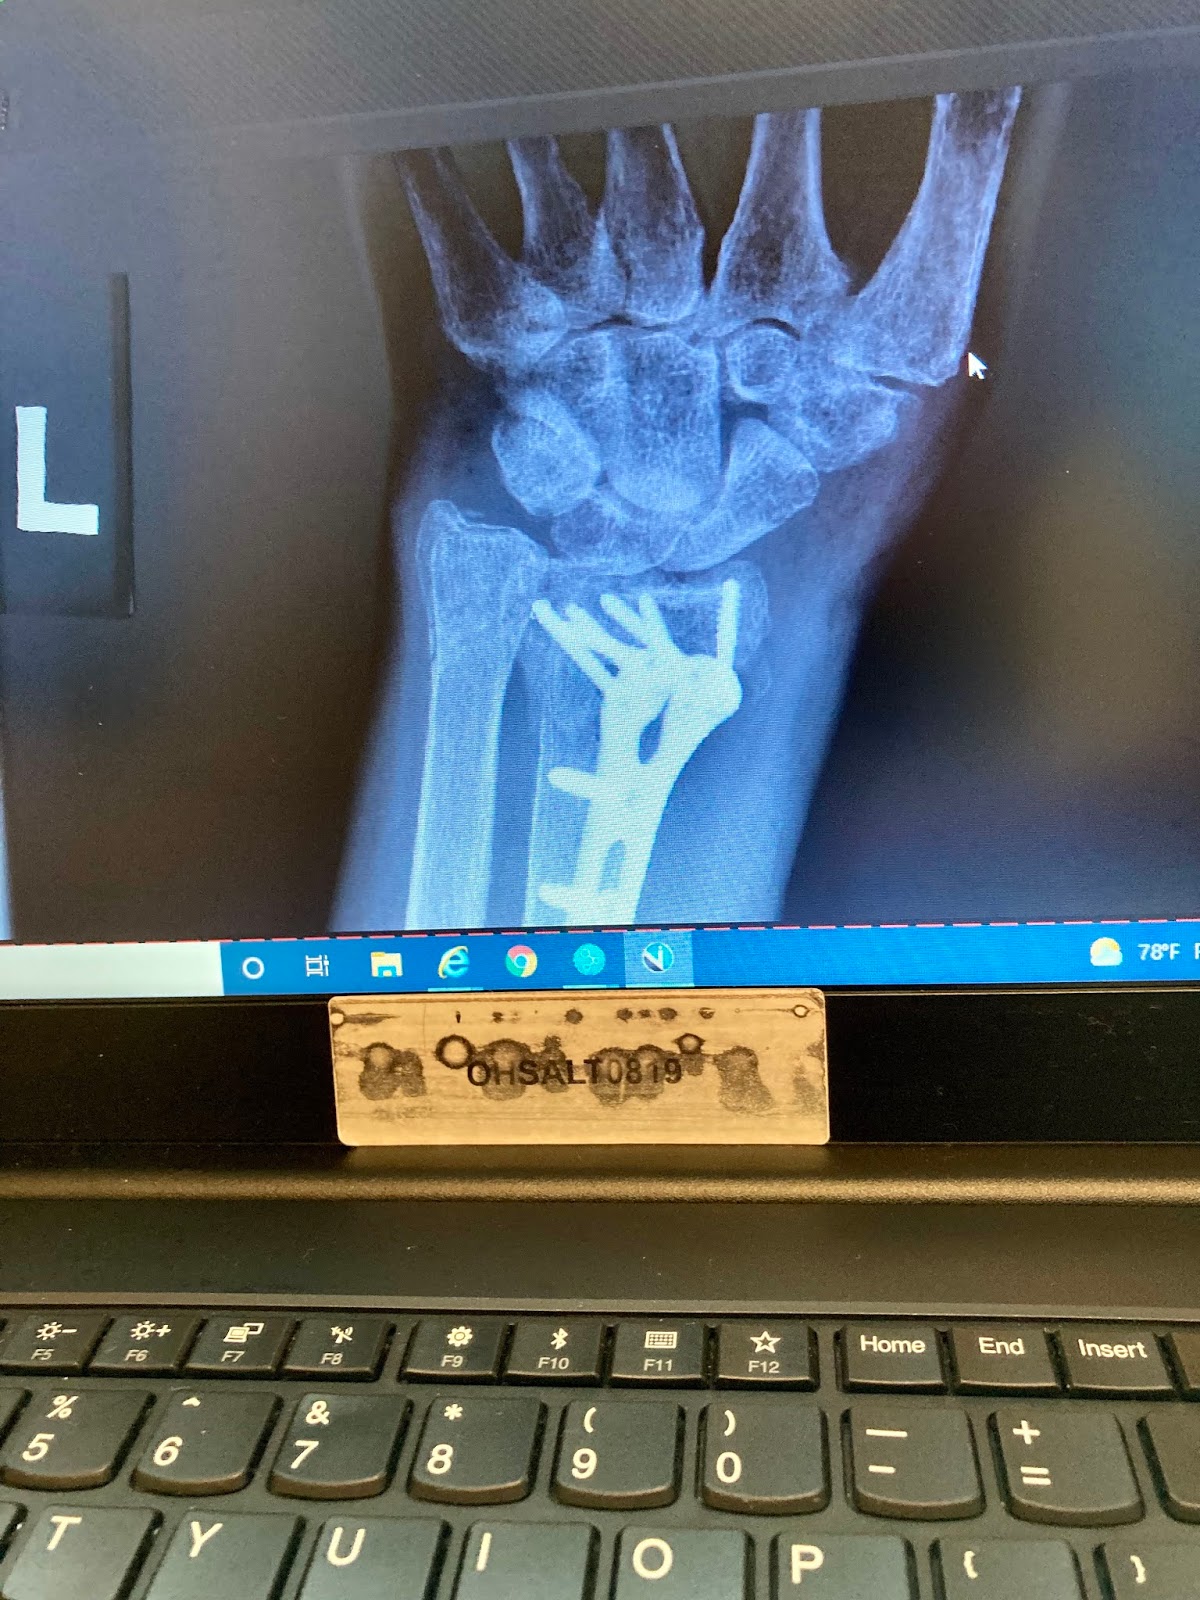

At Thursday's appointment, I requested the surgical report so now I know the name of the inserted device. The image below is enlarged a bit on her laptop, her being Dr. Patel's PA, so a few of the lower screws are cut off from sight.